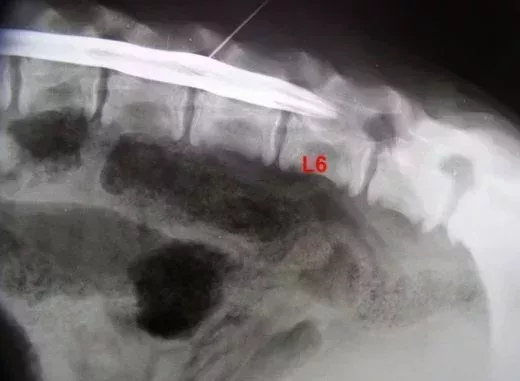

Je jette un oeil à la radio de la myelo passée quelques semaines auparavant pour constater que le cône médullaire n’est pas bas (= après S1) comme le demanderait une FTM élevée, mais qu’au contraire, le liquide de contraste qui s’arrête au cul de sac dure mérien se retrouve vers L5…ou L6 selon les clichés….tous pris au cours de la même anesthésie. De là à dire que le positionnement de l’ensemble varie selon les positions….?

voici ces trois clichés dans l’ordre que je pense chronologique, suivis d’un cliché des premières cervicales qui ne me semblent pas bien alignées effectivement comme on pourrait s’y attendre.

Le sac dure mérien varie d’une vertèbre et demi dans sa terminaison entre le début et la fin de l’anesthésie…comment interpréter cela ?? Une simple migration du liquide de contraste ?